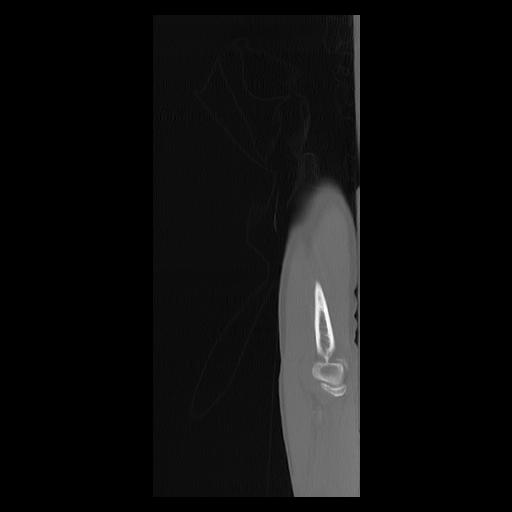

33 PULMON,CE,Sagittal,3.000,PULMON,Sagittal,